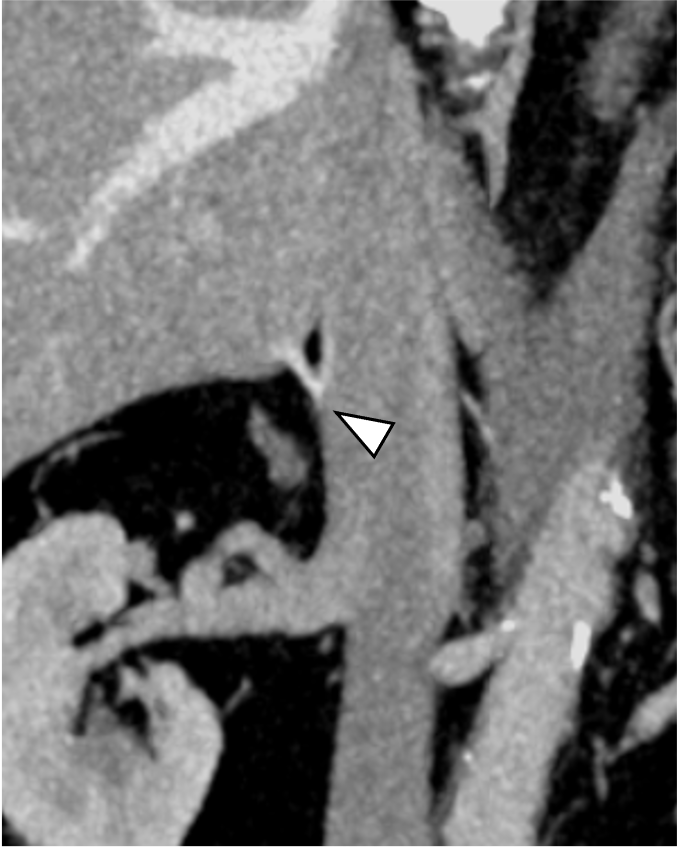

原発性アルドステロン症は, 治癒可能な二次性高血圧であり, 本態性高血圧より脳・心血管, 腎合併症の頻度が高く, その診断および治療の重要性が指摘されている, 片側性のアルドステロン症の場合, 外科的切除によりアルドステロン過剰の正常化, 高血圧および臓器障害の改善・防止が期待できる, このため, 手術が考慮される場合には副腎静脈サンプリングによる機能的局在診断を行う, 原発性アルドステロン症診療ガイドライン20211)では, この副腎静脈サンプリングの成功率を向上させる方法の一つとして, ダイナミックmulti-detector row CT(MDCT)が推奨されている, MDCTでは, 横断像やMPR(Multi planar Reconstruction)を用いて, 副腎静脈の走行やvariationの確認などを行うが, これに加え当院では,仮想透視画像を作成し, 右副腎静脈の下大静脈開口部のレベルや, 副肝静脈との位置関係など, 立体的な解剖学的把握を行っている, その結果, サンプリング時に, スムーズかつ的確なカテーテル操作が可能となる.

本検査における後期動脈相は, 右副腎静脈と下大静脈との合流部, また左副腎静脈と下横隔静脈, 腎静脈との合流部の形態評価が求められる重要な撮影時相である. そのため30sec注入時間固定法とbolus tracking法の併用を行い, 腹部下行大動脈において+100HUのCT値上昇をトリガーとし, 20secのdelay timeにて後期動脈相の撮影を行っている. その後の門脈優位相は, トリガーから40secの撮影とし, 主に副肝静脈と下大静脈との合流部の形態評価が目的とされる. 造影コントラスト向上のため. 可能な限り低管電圧撮影が行えるよう留意している. なお, 本症例は, 造影剤量がプロトコルより少ない症例であったが, 低管電圧撮影や後期動脈相の最適な撮影タイミングにより, 副腎静脈を良好に描出し得た.